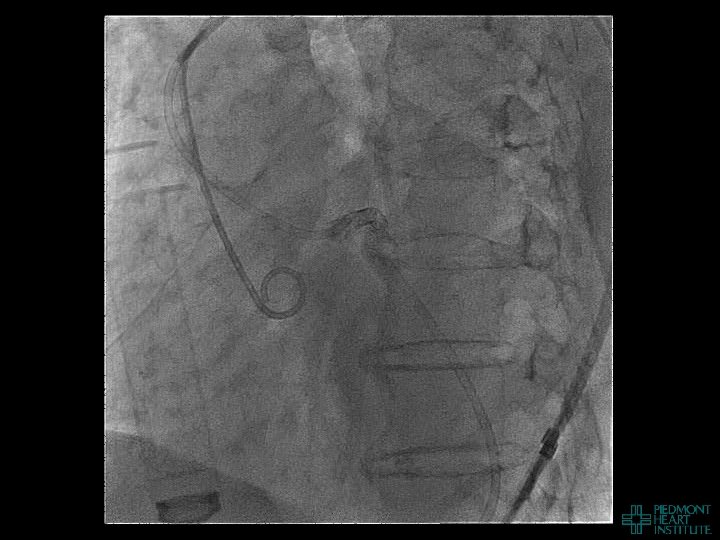

Case Example 3